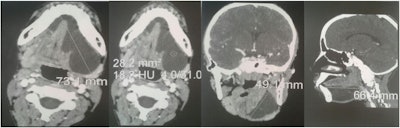

Closer inspection revealed a blue ovoid lesion that was painless with no secretion. A computed tomography (CT) scan confirmed the cystic mass, which clinicians determined needed to be removed.